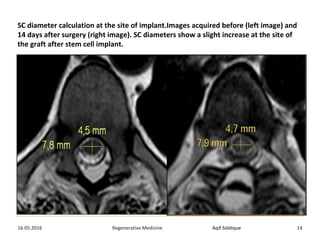

Results

• A slight segmental increase of the spinal cord volume with no

contrast enhancement after gadolinium injection at the

injection site of the cells was observed in all patients after

surgery.

• Measurements of the AP diameter of the spinal cord of all

cases were increased by up to two and a half-fold above the

baseline measurement at all post-operative time points

probably due to the MSC suspension.

SC diameter calculation at the site of implant.Images acquired before (left image) and

14 days after surgery (right image). SC diameters show a slight increase at the site of

the graft after stem cell implant.